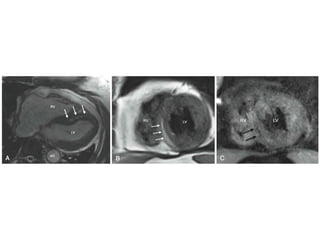

• #23 Step 1: Images are obtained along the scanner axes (sagittal, coronal, and axial; 1A,1B, and 1C, respectively). Step 2: From a pseudo four-chamber long-axis view (usually from the axial image), one prescribes a perpendicular plane through the approximate apex, which results in an approximate two-chamber view. Step 3: Another perpendicular plane is prescribed through the apex, which results in a true long-axis view (usually four chamber). Step 4: A perpendicular plane, bread-loafing the heart, delivers the true short-axis plane.

• #30 before arrival of contrast (frame 1); contrast in RV cavity (frame 12); contrast in LV cavity (frame 22); peak contrast in LV myocardium (frame 30), showing normal perfusion in the septum (open arrowhead) and abnormal perfusion in the inferolateral wall (solid arrowhead); and the contrast wash-out phase (frame 50).

• #33 Before contrast administration, there are minimal differences in inherent tissue T1 and T2 between normal and infarcted myocardium, thus infarction is poorly delineated (top panel). After gadolinium administration, the T1 of infarction (although not T2) is markedly shortened, leading to clear delineation on the T1-weighted image (bottom panel). T1-weighted images were acquired using an inversion recovery gradient echo sequence. T2-weighted images were acquired using a dark blood turbo spin echo sequence.